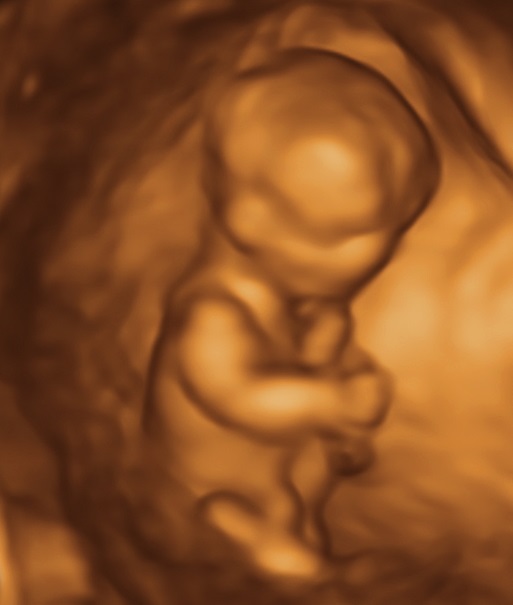

but Doc was unsure. 12 week, nt scan... thanks!:think:

I don't see a visible nub but what a cute baby!!

the skull looks boyish though...